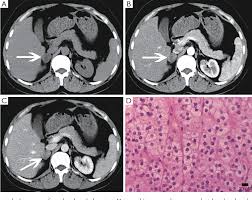

Diagnostic Value Of Delayed Washout Rate Of Contrast Enhanced Multi Detector Computed Tomography In Adrenal Incidentalomas Sciencedirect

Diagnostic Value Of Delayed Washout Rate Of Contrast Enhanced Multi Detector Computed Tomography In Adrenal Incidentalomas Sciencedirect from ars.els-cdn.com

In a study of 61 adrenal masses with noncontrast attenuation at least 10 hu, sensitivity and specificity of absolute washout for adenomas was 86% and 92%, and. A key objective is the reliable distinction of. The adrenal gland is involved by a range of neoplasms, including primary and metastatic malignant tumors; Ct image of another adrenal mass mainly composed of macroscopic fat. Radiologist can establish a definitive diagnosis for most adrenal masses (i.e. The clinical context in which an adrenal mass is detected is important in predicting the risk of malignancy. Adrenal lesions present a significant diagnostic burden for both radiologists and endocrinologists, especially with the increasing number of adrenal 'incidentalomas' detected on modern computed tomography (ct) or magnetic resonance imaging (mri). Pathologic conditions, pearls, and pitfalls. Mri is superior to ct in the evaluation of cardiac masses. Adrenal masses <1 cm do not require further investigation. Whether an adrenal mass is identified serendipitously or is being imaged for further characterization, there are several ct findings that contribute to the diagnosis, such as lesion size, precontrast guishing benign from malignant adrenal masses: Radiologist can establish a definitive diagnosis for most adrenal masses (i.e. Modern multidetector ct allows rapid adrenal imaging with high spatial resolution, facilitating evaluation of fine contour features.

Finally, a number of nonadrenal pathologic conditions have been reported to mimic adrenal masses at ct. Mri is superior to ct in the evaluation of cardiac masses. The adrenal gland is involved by a range of neoplasms, including primary and metastatic malignant tumors; However, the most common tumor detected is the incidental benign adenoma. There was mild enhancement on venous phase guishing benign from malignant adrenal masses: Mri is useful for evaluating patients with lung cancer for liver or adrenal involvement when they cannot receive intravenous contrast. Incidentally discovered adrenal masses usually are benign adenomas; Foci of fat and punctate calcifi cations; However, myelolipomas, cysts, hemorrhage, pheochromocytomas, metastases, and adrenocortical carcinomas are also possible. Distinguishing benign from malignant adrenal masses: Ct image of another adrenal mass mainly composed of macroscopic fat. Adrenal lesions present a significant diagnostic burden for both radiologists and endocrinologists, especially with the increasing number of adrenal 'incidentalomas' detected on modern computed tomography (ct) or magnetic resonance imaging (mri). Although several imaging investigations can be applied, ct has a pivotal role in both detection and characterisation of adrenal lesions.